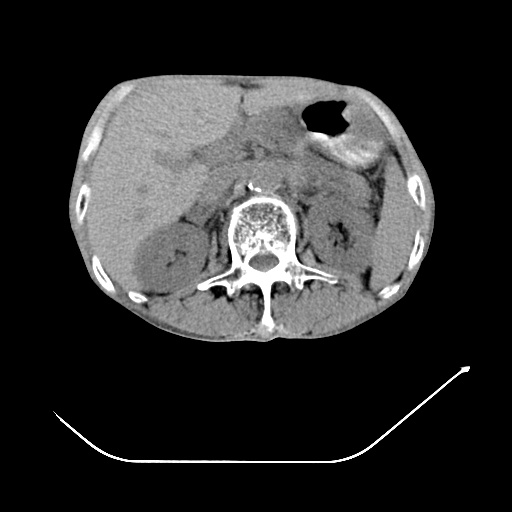

以下是引用zsl6918在2008-8-25 21:55:00的发言:[br]符合右肺周围性肺癌并肺内转移,左肺结核球。双肺肺气肿。腰椎附件转移。

以下是引用随光逐影在2008-8-25 22:03:00的发言:[br]1)考虑右肺下叶周围性肺癌并肺内转移,腰椎附件转移。2)左上肺结核(结核球形成)。3)双肺肺气肿(多发肺大泡形成)。4)双肺门区及纵隔内多发淋巴结钙化。